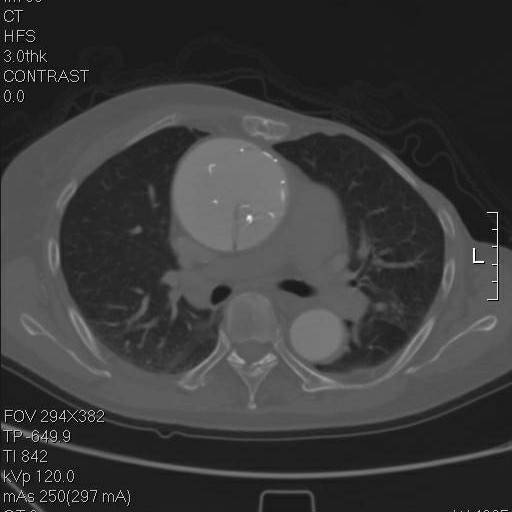

这个层面,支架终于完全在真腔内了,但假腔基本没有闭合。